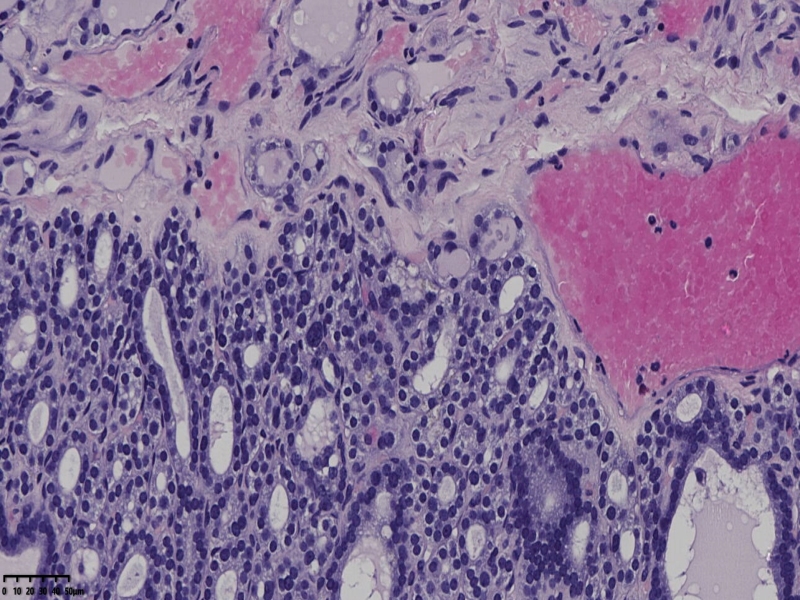

部分区域瘤组织与周围甲状腺组织分界明显,没有包膜样结构,滤泡结构为主,细胞异型明显。

会诊结果:(左叶甲状腺近峡部)甲状腺肿瘤,考虑为具有RAS核的乳头状癌,建议免疫组化及基因检测。